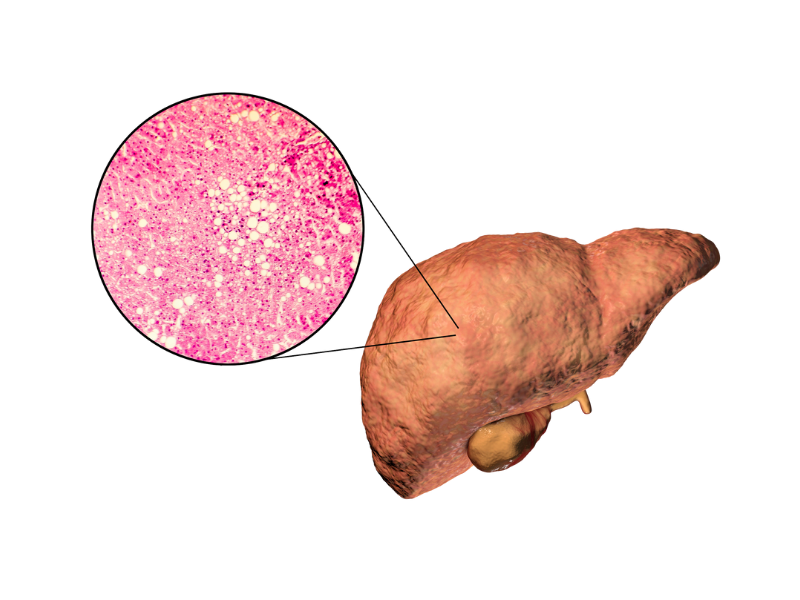

Liver transplant is a complex but life-saving procedure for patients with severe liver disease, liver failure, or certain liver cancers. It involves replacing a diseased liver with a healthy one from a living or deceased donor. At our Liver Transplant and HPB Surgery Care center, we provide comprehensive care for both adults and children, ensuring safety, precision, and excellent outcomes.